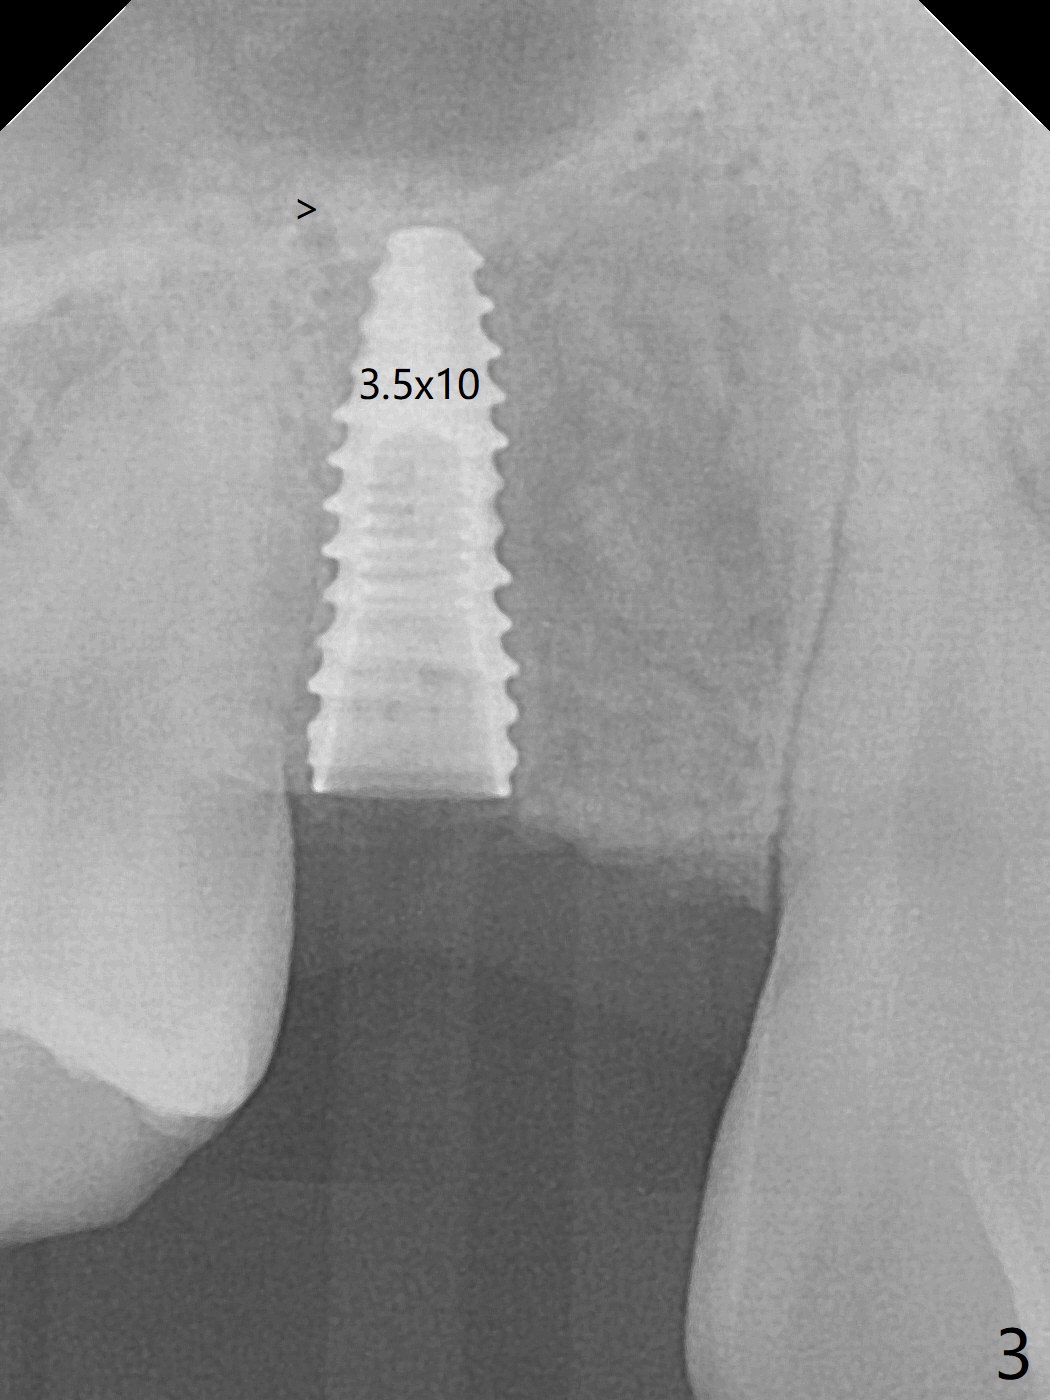

18岁男,本月底到外州上大学,急于十九岁前完成治疗,保险可以多付些。术前检查显示双侧尖牙(图一,二 6,11)根尖,侧切牙牙槽嵴萎缩(*),尖牙、侧切牙之间颊侧做垂直切口,骨膜下潜行分离,在尖牙根尖隧道植骨,然后使用导板,植入窄植体(图四至六),接近或者穿过上颌窦底板(图三,四箭头),骨粉(粘性骨块做的不成功,图五,六 *)好像覆盖暴露的螺纹。再次补充隧道骨粉后,放置修复基台(图七,八),调整后(图九),取模做临时悬臂桥,临床上有些困难分配尖牙,侧切牙比例。术后4个月左侧植体愈合正常(图十,十一),而右侧感染。